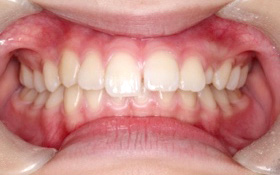

1叢生

主訴:前歯のガタガタが気になる(患者初診時年齢:23歳11か月)

診断名:叢生

治療に用いた主な装置:マルチブラケット装置

抜歯部位:非抜歯

治療期間:2年6か月

治療費概算およびリスク副作用:当科で設定している治療費に準じ、リスク副作用についても日本矯正歯科学会Hp掲載内容を説明(上記参照)

動的治療終了時